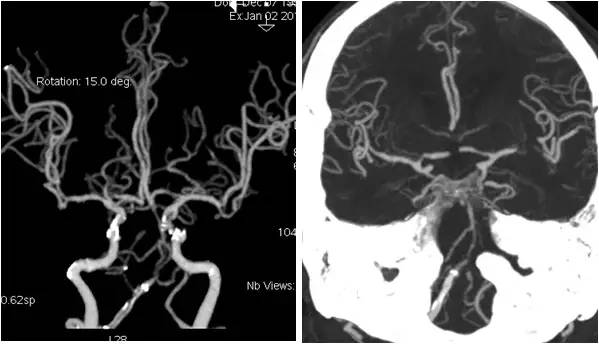

术后复查头颅CTA:右椎动脉V4段支架通畅(图12)。

图12